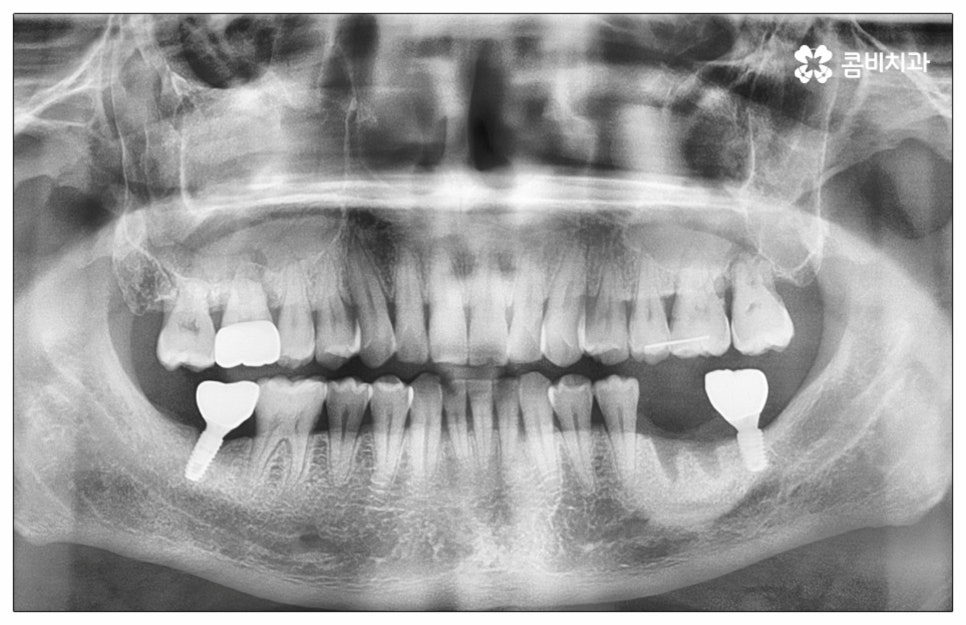

예전에는 이런 상황에서 틀니를 많이 이용하였으나 저작력 회복이 본래 자신의 치아 대비 20~30% 정도 밖에 되지 않고 잦은 탈락 위험 및 이물감, 잇몸을 눌러 장기적으로 잇몸뼈가 내려앉을 수 있다는 점 등 여러 가지 불편함이 있어 요즘은 임플란트 시술을 선호하시는 분들이 더 많아지고 있어요. 임플란트란 인체에 무해하며 잇몸뼈와 잘 결합하는 인공 치근을 잇몸뼈에 직접 식립하고 그 위로 기둥이 되는 중간 지대주와 치아 머리가 되는 크라운 보철물을 연결하여 인공 치아를 만들어 주는 시술을 말하는데, 자연 치아의 80% 정도 저작력 회복이 가능하기 때문에 식사를 할 때 음식을 크게 가리지 않아도 된다는 점 그리고 심미적으로 봤을 때 주변 치아와 자연스럽게 어우러진다는 점 때문에 각광을 받고 있습니다. 게다가 건강 보험 가입자이면서 만 65세 이상 부분 무치악 환자라면 평생 임플란트 2개까지 보험 적용을 받아 비용 부담을 줄일 수 있기 때문에 더욱 더 수요가 늘어나 이제는 치아 상실에 대체하는 대표적인 방법으로 임플란트 시술이 꼽히고 있는데요.

많이 대중화 되었다고 해도 임플란트 수술 자체가 술자의 숙련도에 크게 영향을 받는 복잡하고 고난도의 진료인 것은 틀림이 없기 때문에 담당 의료진이 해당 분야 임상 경험이 풍부한지, 뛰어난 기술력과 노하우를 가지고 있는지 꼼꼼하게 체크해 보실 필요가 있어요. 특히 노년층의 경우 당뇨, 고혈압 등 만성 질환을 앓고 있는 경우가 많아 혹시 상시 복용하고 있는 약이 있는지, 현재 환자 개개인의 상태는 어떤지, 사전 처치가 필요한 부분은 없는지 등등 수술 조건을 좀 더 까다롭게 평가한 후 환자분들과 이에 대해 충분히 상담하고 맞춤형 치료 계획을 세워 진행해야 하며 이를 위해 3D CT 와 같은 디지털 검진 장비를 통해 구강 내부 구조를 면밀하게 살피고 방대한 임상 데이터를 축적한 정품 임플란트 재료를 이용하여 연령이나 회복 정도를 살펴보면서 체력적 부담을 줄이는 방향으로 무리하지 않게 식립하는 것이 무엇보다 중요하다고 할 수 있습니다.

임플란트 치아는 관리를 철저하게 해 주면 거의 반영구적으로 쓸 수 있으니 환자분들의 입장에서 구강 위생을 깨끗하게 유지시키고 또한 정기적으로 치과에 내원하셔서 스케일링 및 검진 진료를 받으시면 도움이 될 거예요. 임플란트는 자연 치아와 주변 조직이 다르기 때문에 특히 잇몸 질환을 주의해야 하며 수직력에는 강하지만 수평력에는 약한 특징을 가지니 혹시라도 이갈이 등의 습관을 가지고 있다면 이를 고칠 수 있도록 노력하시는 것이 임플란트 치아를 보다 오랜 기간 건강하게 사용하실 수 있는 지름길이라고 할 수 있습니다.